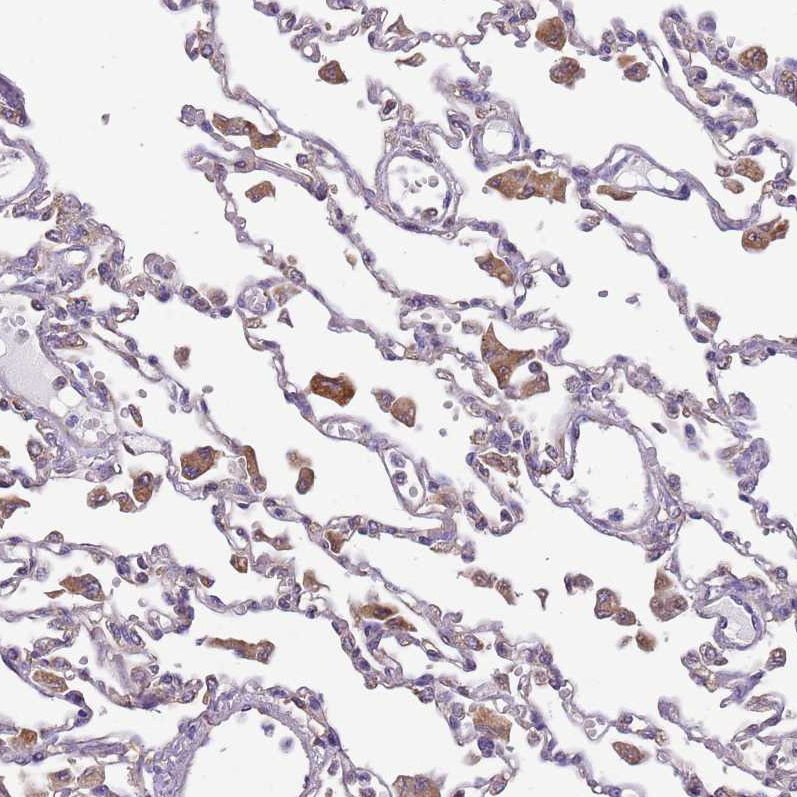

Immunohistochemical staining of human placenta shows weak to moderate cytoplasmic positivity in trophoblastic cells.